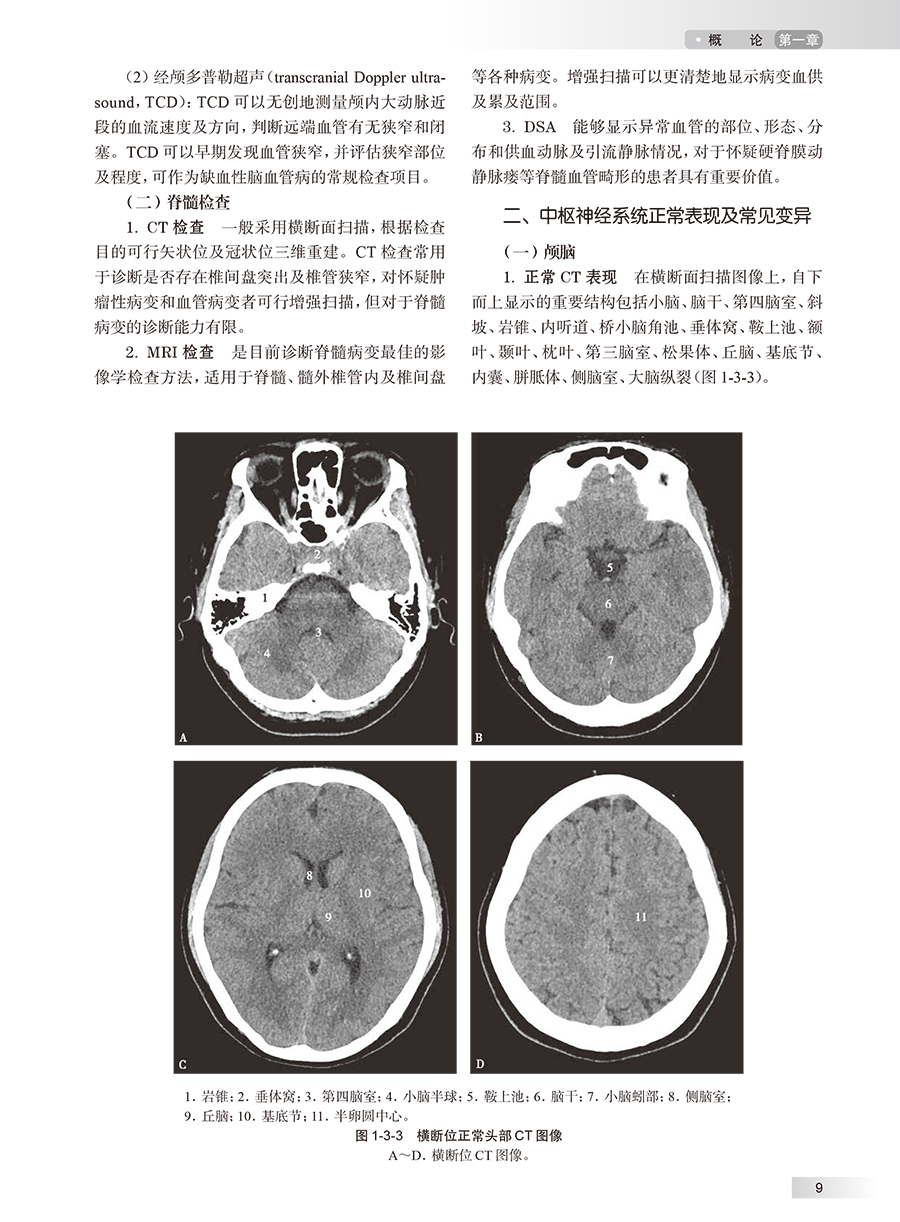

第一章 概论/ 1 第一节 编写思路 / 1 第二节 神经系统病理生理特点 / 1 一、 中枢神经系统解剖 / 1 二、 神经系统疾病的病理生理特点 / 4 第三节 神经系统疾病共性规律 / 6 一、 中枢神经系统影像学检查方法 / 6 二、 中枢神经系统正常表现及常见变异 / 9 三、 中枢神经系统基本病变的影像征象 / 11 第二章 临床常见症状与体征/ 15 第一节 头痛 / 15 一、 定义及概述 / 15 二、 临床表现与诊断检查 / 15 三、 影像学在继发性头痛中的应用 / 16 第二节 眩晕 / 17 一、 定义及概述 / 17 二、 临床表现与诊断检查 / 17 三、 影像学在中枢性眩晕中的应用 / 19 四、 影像学在周围性眩晕中的应用 / 19 第三节 意识障碍 / 20 一、 定义及概述 / 20 二、 临床表现及诊断检查 / 20 三、 影像学在昏迷中的病因诊断的应用 / 21 第三章 大脑半球病变/ 24 第一节 灰质病变 / 24 一、 局灶性病变 / 24 二、 弥漫性病变 / 35 第二节 白质病变 / 52 一、 局灶性病变 / 52 二、 弥漫性病变 / 78 第三节 灰白质交界区病变 / 97 一、 环形强化征 / 97 二、 鸡冠花征 / 99 三、 囊+ 头节征 / 101 四、 隧道征 / 102 五、 子母环征 / 104 六、 日光带征 / 105 第四章 基底节区病变/ 109 第一节 单侧病变 / 109 一、 有占位效应的病变 / 109 二、 无占位效应的病变 / 114 三、 负占位效应的病变 / 119 四、 特殊征象 / 120 第二节 双侧病变 / 134 一、 有占位效应的病变 / 134 二、 无占位效应的病变 / 140 三、 负占位效应的病变 / 145 四、 特殊征象 / 146 第五章 丘脑病变/ 152 第一节 单侧病变 / 152 一、 有占位效应的病变 / 152 二、 无占位效应的病变 / 155 三、 负占位效应的病变 / 157 第二节 双侧病变 / 159 一、 有占位效应的病变 / 159 二、 无占位效应的病变 / 168 三、 负占位效应的病变 / 177 四、 特殊征象 / 180 第六章 下丘脑病变/ 184 一、 实性病变 / 184 二、 囊性病变 / 191 三、 特殊征象 / 196 第七章 松果体区病变/ 198 一、 实性病变 / 198 二、 囊性病变 / 204 三、 特殊征象 / 208 第八章 脑干病变/ 212 第一节 中脑病变 / 212 一、 有占位效应的病变 / 212 二、 无占位效应的病变 / 214 三、 负占位效应的病变 / 215 四、 特殊征象 / 217 第二节 脑桥及桥臂病变 / 219 一、 有占位效应的病变 / 219 二、 无占位效应的病变 / 223 三、 负占位效应的病变 / 226 四、 特殊征象 / 229 第三节 延髓病变 / 232 一、 有占位效应的病变 / 232 二、 无占位效应的病变 / 234 三、 负占位效应的病变 / 238 第九章 小脑半球病变/ 240 第一节 皮层病变 / 240 一、 弥漫性病变 / 240 二、 局灶性病变 / 243 三、 特殊征象 / 247 第二节 白质病变 / 251 一、 弥漫性病变 / 251 二、 局灶性病变 / 254 三、 特殊征象 / 260 第三节 小脑蚓部病变 / 261 一、 有占位效应的病变 / 261 二、 负占位效应的病变 / 264 三、 小脑蚓部缺如 / 264 第十章 脑室系统病变/ 268 第一节 侧脑室病变 / 268 第二节 第三脑室病变 / 274 第三节 中脑导水管病变 / 280 第四节 第四脑室病变 / 281 第五节 脑室内弥漫性病变 / 291 第六节 室管膜下病变 / 296 第七节 脑室扩大 / 297 第十一章 颅内血管病变/ 303 第一节 动脉血管病变相关征象 / 303 一、 血管高密度征 / 303 二、 磁敏感血管征 / 304 三、 岛带征 / 305 四、 错配征 / 307 五、 T2FLAIR 弥散错配征 / 308 六、 灰白质模糊征 / 310 七、 常春藤征 / 311 八、 三区域征 / 314 九、 串珠样改变 / 315 第二节 静脉血管病变相关征象 / 317 一、 FLAIR 血管高信号征 / 317 二、 空三角征 / 318 三、 海蛇头征 / 319 四、 爆米花征 / 320 五、 开花征 / 321 第十二章 鞍区及鞍上病变/ 324 第一节 鞍区病变 / 324 一、 有占位效应的病变 / 324 二、 无占位效应的病变 / 329 三、 雪人征 / 332 第二节 鞍上病变 / 333 一、 鞍上实性病变 / 333 二、 鞍上囊性病变 / 337 第十三章 海绵窦区病变/ 344 第一节 有占位效应的病变 / 344 第二节 无占位效应的病变 / 351 第三节 阴阳征 / 355 第十四章 桥小脑角区病变/ 359 第一节 实性病变 / 359 第二节 囊性病变 / 366 第三节 特殊征象 / 372 第十五章 颈静脉孔区病变/ 374 第一节 实性病变 / 374 第二节 囊性病变 / 379 第三节 特殊征象 / 383 一、 胡椒盐征 / 383 二、 哑铃征 / 385 三、 阴阳征 / 388 第十六章 脑膜病变/ 391 第一节 硬脑膜病变 / 391 一、 局灶性病变 / 391 二、 弥漫性病变 / 395 三、 脑膜尾征 / 399 第二节 蛛网膜下腔病变 / 400 一、 局灶性病变 / 400 二、 弥漫性病变 / 403 第三节 软脑膜病变 / 405 第十七章 颅骨病变/ 411 第一节 局限性病变 / 411 第二节 弥漫性病变 / 416 第十八章 脊柱与脊髓病变/ 421 第一节 髓内病变 / 421 一、 有占位效应的病变 / 421 二、 无占位效应的病变 / 428 三、 负占位效应的病变 / 433 四、 特殊征象 / 437 第二节 髓外硬膜下病变 / 441 一、 局灶性病变 / 441 二、 弥漫性病变 / 447 三、 特殊征象 / 452 第三节 硬膜外病变 / 454 一、 局灶性病变 / 454 二、 弥漫性病变 / 458 三、 特殊征象 / 463 中英文名词对照索引/ 473 登录中华临床影像征象库步骤/ 475